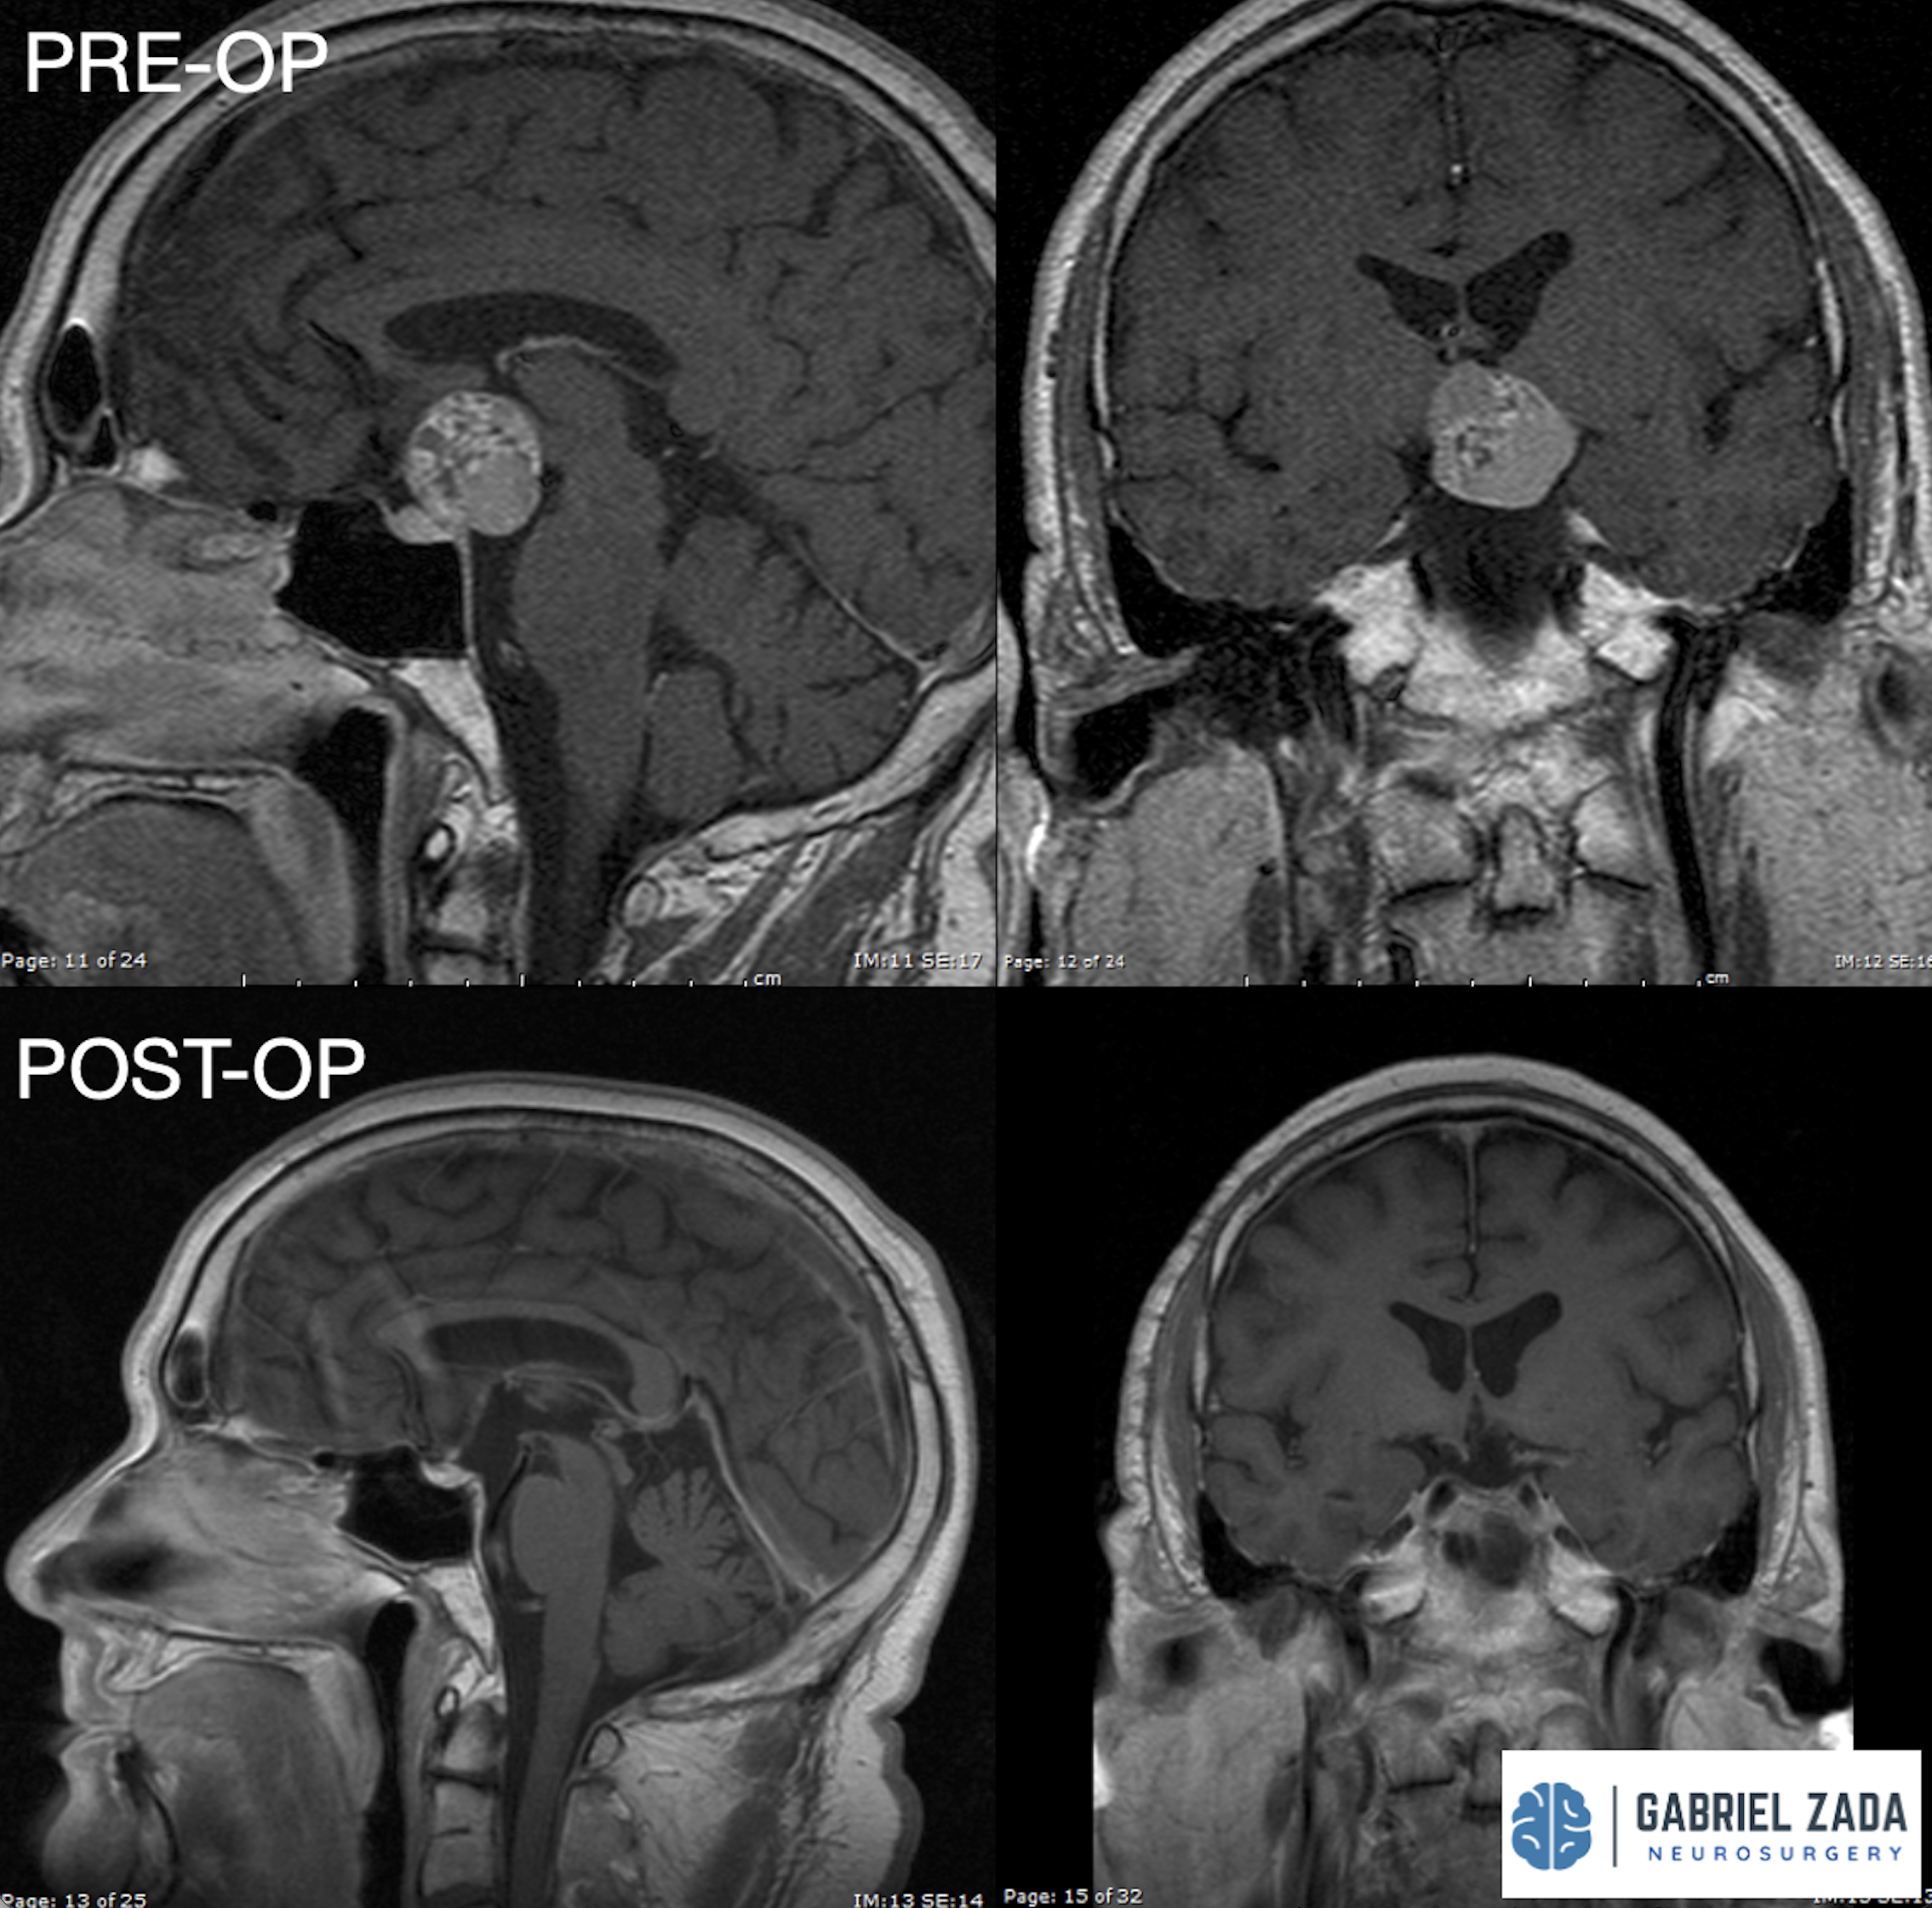

Explore this comprehensive gallery featuring pre‑ and post‑operative imaging of patients with skull‑base tumors treated by Gabriel Zada, MD, MS, FAANS, FACS. These cases highlight Dr. Zada’s expertise in advanced neurosurgical techniques and outcomes.

*Representative cases shown for educational purposes. All images de-identified. Individual results vary.